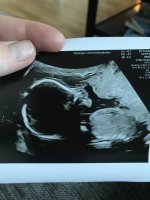

Termindato på meg i morgen, men frøkna er født for 6mnd siden. Jeg skulle visst bare bli englemamma til ei jente, for i magen boltrer det seg en lillebror![]()

Og jeg er evig takknemlig for at alt ser helt perfekt ut på UL i dag med skikkelig anatomisk gjennomgang, fra hodet til tær, og alt som var fryktelig galt er helt perfekt nå. Er 12+2 i dag, men jordmor målte meg til 12+4, så termin rundt 28 april. Spent på om sykehuset finner det samme på ultralyd neste onsdag. Enn hvor glad jeg er for at jeg har en frisk lillebror i magen, så er jeg ett lite snev skuffet. Skuffet over at jeg ikke får min lille prinsesse Maja, som jeg alltid har drømt om. Vet at jeg blir like glad i lillebror som jeg er i storebror og gutt kan jeg jo, men jeg drømte liksom om å få en jente. Men min jente var syk…